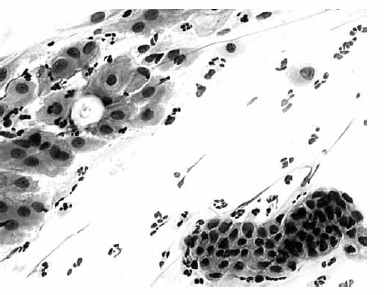

Nas questões de números 46 a 60, assinale a alternativa que melhor corresponde ao diagnóstico do quadro microscópico apresentado.

Metaplasia escamosa; células endocervicais reativas.

Células escamosas com atipias de significado indeterminado (ASCUS).

Atipias de células glandulares.

Células endometriais.